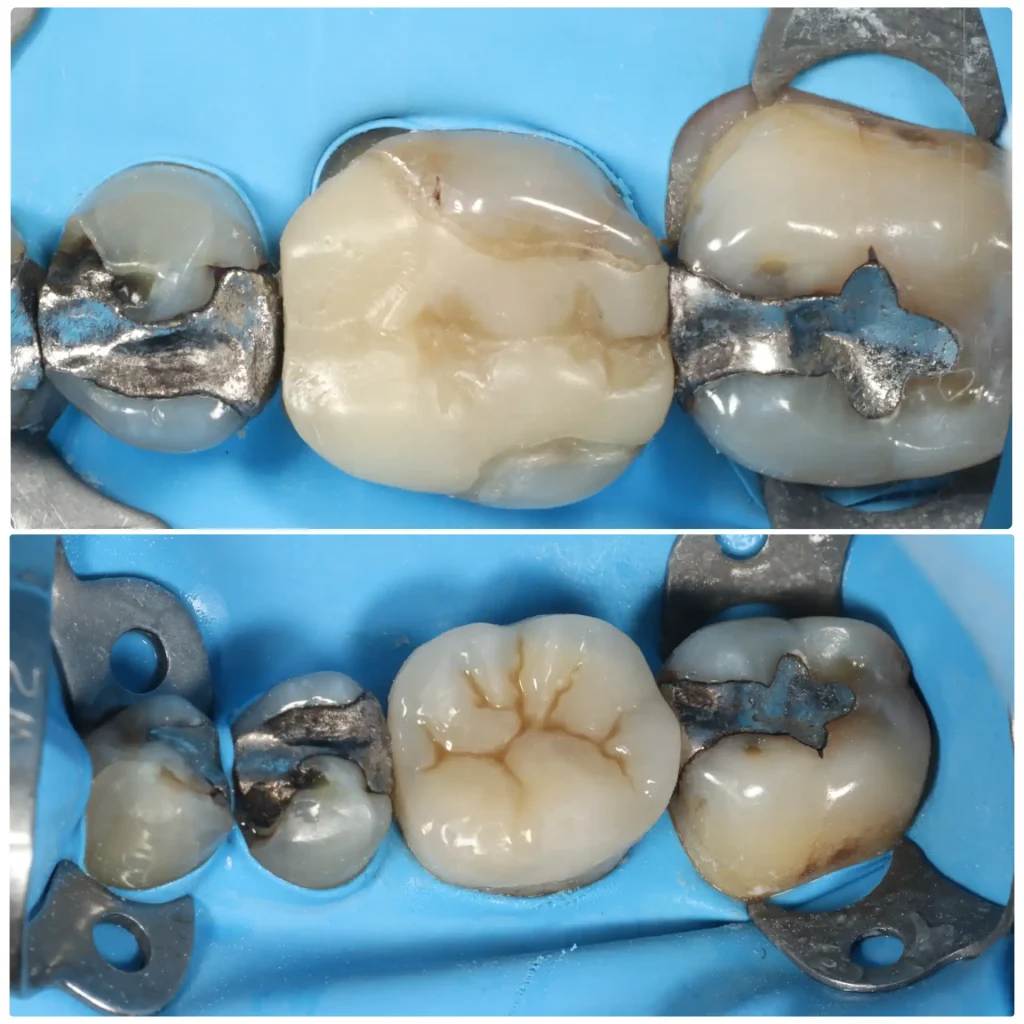

Case studies